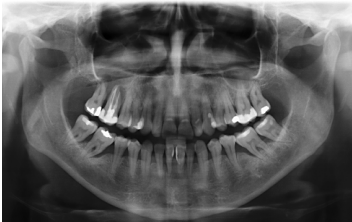

Finalmente, podemos observar la estabilidad de ambos tratamientos en la radiografía final a los 8 años, donde ambos se mantienen estables sin pérdidas óseas (Figura 13)